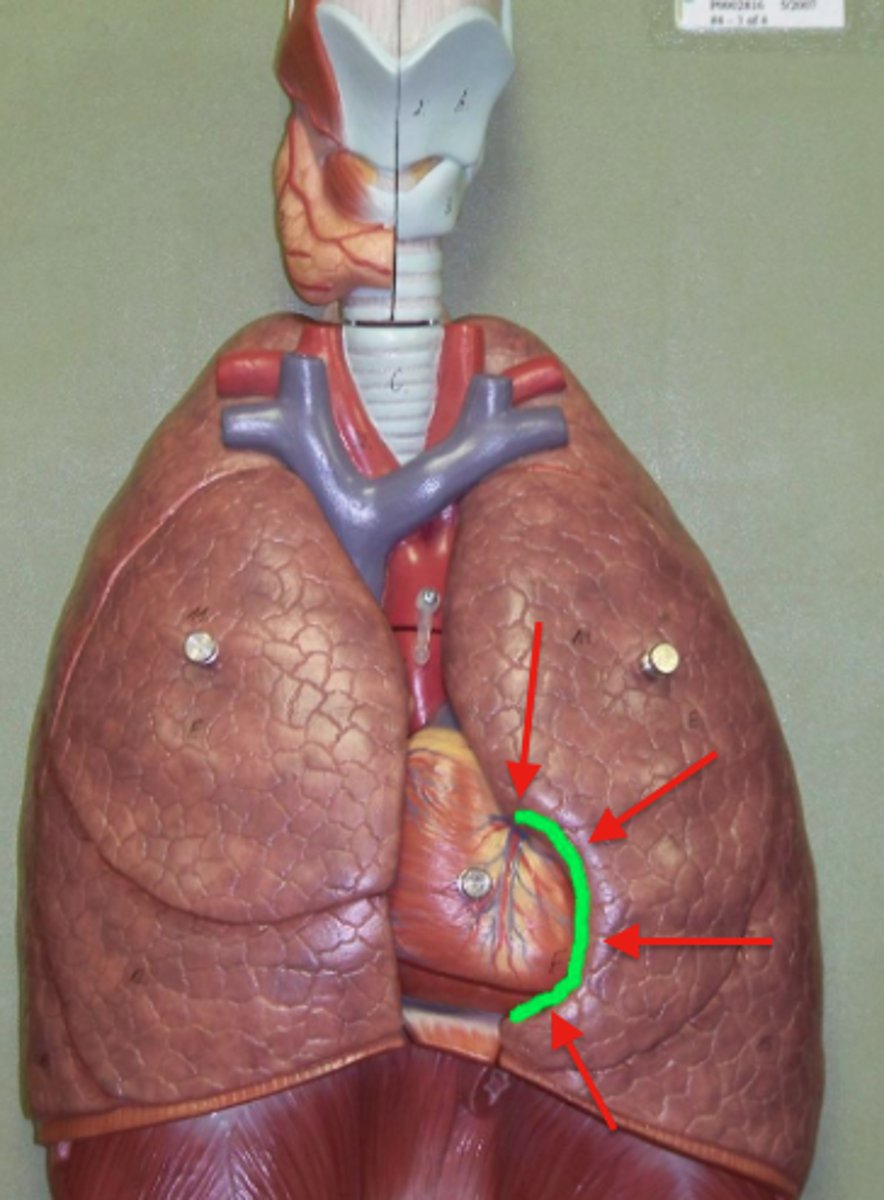

hilum

lingula

a tongue-like extension of the left superior lobe projects anteriorly over the heart

cardiac notch

a concave space on the left lung in which the heart lies